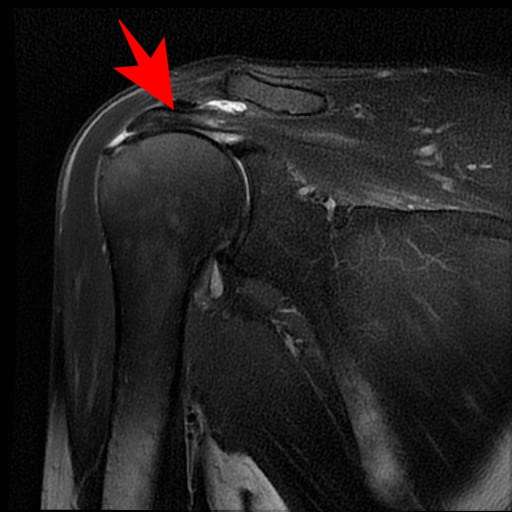

肩腱板断裂

40歳以上の男性に好発します(男女比6:4)。発症ピークは60代であり、来院理由の多くは寝ていられないほどの痛み(夜間痛)が動機になります。

原因・病態

肩関節腱板は4つの筋肉(棘上筋・棘下筋・小円筋・肩甲下筋)で構成されており、ローテーターカフと言われています。これば上腕骨と肩甲骨をつなぐ板状の腱で、腕を上げたり下げたりする時に上腕骨頭が肩甲骨の関節窩とずれないように保つ働きがあります。

これが損傷・断裂すると腕の上げ下げで肩関節の支点がとれなくなり、痛みや引っかかりなどの症状が出ます。

加齢による腱板の変性を基盤として、転倒など様々な程度の外傷が加わって断裂することが考えられています。腱板は肩峰と上腕骨頭の間に挟まれる形をしており反復的な挟み込みストレスを受けやすいことも一因です。

※炎症しているところが白く映っています。